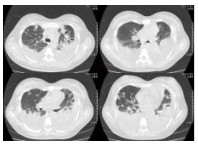

入院后给予抗感染、液体复苏、保肝、补充白蛋白、提升白细胞、输注血小板等对症支持治疗,生命体征逐渐稳定,但患者胸片以及胸部CT仍提示呈进展状态,双肺弥漫性渗出较前明显,肺组织出现“空洞”,并呈进行性破坏,见图 2~3。体温持续波动在38~40℃。入院第8天胸CT提示双侧胸腔积液, 入院第21天胸CT提示双肺渗出及大小不一的“空洞”, 出院时胸部CT,左侧肺气囊样变(图 4)。

| 图 2 入院第8天胸部CT |

| 图 3 入院第21天胸部CT |